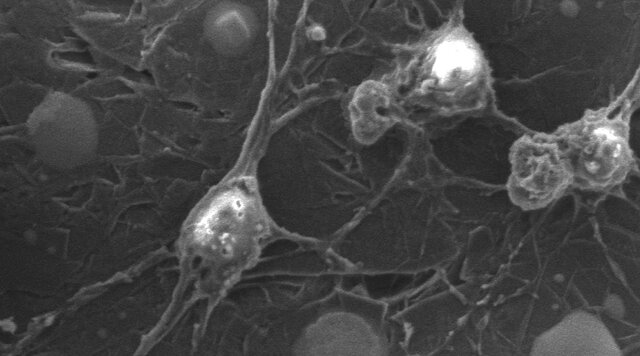

سلولهای بنیادی به دلیل توانایی تبدیل شدن به همه انواع سلول، نویدبخش پیشرفت در حوزه پزشکی ترمیمی هستند. این فرآیند طبیعی را میتوان برای جایگزینی سلولهای مرده یا آسیبدیده با سلولهای جدید و کارآمد مورد استفاده قرار داد.

وقتی صحبت از درمان آسیبهای نخاعی به میان میآید، میتوان از سلولهای بنیادی پیوند زدهشده به اعصاب آسیبدیده استفاده کرد تا به نورونهای کارآمد تبدیل شوند. با وجود این، تبدیل سلولهای بنیادی عصبی در بدن بسیار چالشبرانگیزتر از محیط آزمایشگاه است زیرا ترکیب پیچیده مولکولهای اطراف سلولهای بنیادی در محل آسیب میتواند توانایی آنها را برای درست تبدیل شدن محدود کند.

یکی از مؤثرترین روشها برای بهبود توانایی تبدیل سلولهای بنیادی، فرستادن پالسهای الکتریکی به آنهاست. این روش نه تنها به تبدیل سلولها کمک میکند، بلکه باعث ایجاد سیناپسها یا اتصالات بین نورونها میشود که میتوانند مدت بقای آنها را افزایش دهند.

پژوهشگران پس از بررسی سلولهای در حال رشد روی برچسب گزارش دادند که پالسهای الکتریکی، نسبت سلولهای بنیادی را که به نورونهای بالغ تبدیل میشوند، از ۱۲.۵ درصد به ۳۳.۷ درصد افزایش میدهند.

این گروه پژوهشی نتیجه گرفتند که ترکیب درمان با سلولهای بنیادی و تحریک الکتریکی میتواند تأثیر بسیار بیشتری را در ترمیم بافت عصبی پس از آسیب نخاعی نسبت به استفاده جداگانه از این دو روش داشته باشد.